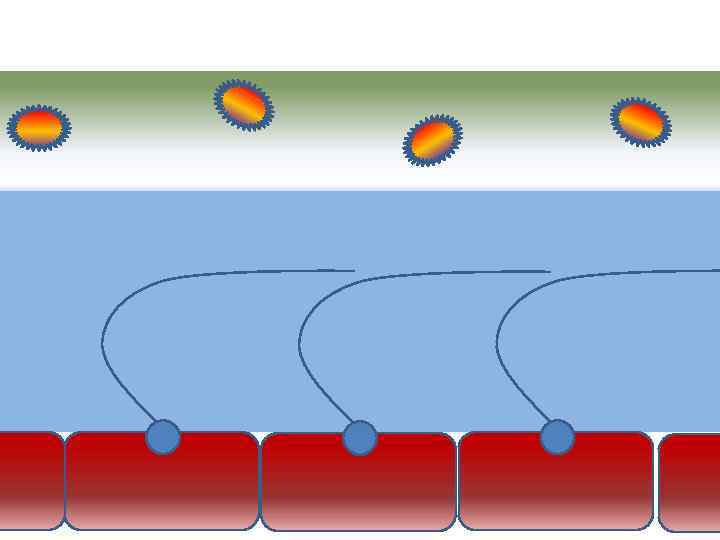

Механизм защиты легкого Слизь (зеленый цвет) нейтрализует и связывает патогенную флору(синий цвет) Слизь – это барьер между клетками и патогенной флорой Слизь – это транспортное средство

Механизм защиты легкого Слизь (зеленый цвет) нейтрализует и связывает патогенную флору(синий цвет) Слизь – это барьер между клетками и патогенной флорой Слизь – это транспортное средство